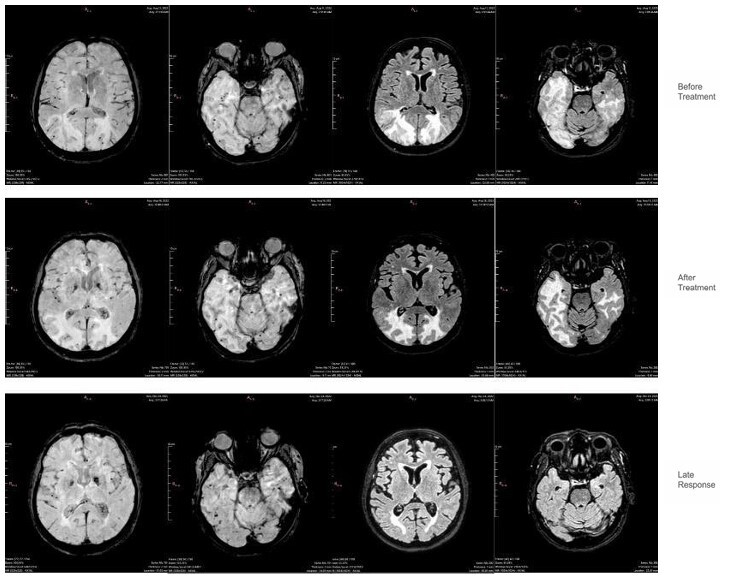

脑淀粉样血管病(CAA)是一种与β-淀粉样蛋白(a β)沉积在皮质和小脑膜血管相关的小血管疾病。传统上通过侵入性方法诊断,现在可以通过先进的成像模式来识别,提高了非侵入性诊断的准确性。一部分患者表现出炎症性表现,称为炎症性脑淀粉样血管病(CAA-RI),其特征是认知能力下降、行为改变和神经功能障碍。本研究重点介绍了两例CAA-RI,其亚急性发作,详细的临床进展,独特的MRI结果符合修订的诊断标准,能够早期怀疑。两例患者在免疫抑制治疗后均有显著改善,这加强了CAA-RI的潜在可逆性和早期识别的重要性。这篇文章强调了先进的影像学在CAA鉴别诊断中的重要性,以及通过及时治疗改善患者预后的潜力。

Cerebral Amyloid Angiopathy (CAA) is a small vessel disease associated with β-amyloid (Aβ) deposition in cortical and leptomeningeal vessels. Traditionally diagnosed through invasive methods, it can now be identified via advanced imaging modalities, enhancing non-invasive diagnostic accuracy. A subset of patients exhibits an inflammatory presentation, termed Inflammatory Cerebral Amyloid Angiopathy (CAA-RI), characterized by cognitive decline, behavioral changes, and neurological deficits. This study highlighted two cases of CAA-RI with subacute onset, detailed clinical progression, and distinct MRI findings consistent with revised diagnostic criteria, enabling early suspicion. Both cases showed significant improvement with immunosuppressive therapy, reinforcing the potentially reversible nature of CAA-RI and the importance of early recognition. This article underscores the relevance of advanced imaging in the differential diagnosis of CAA and the potential for improved patient outcomes with timely treatment.